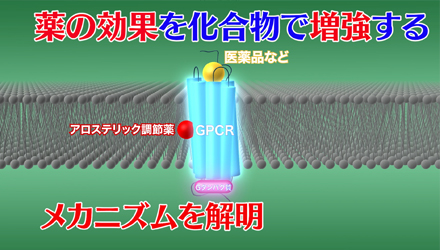

プレスリリース解説 vol.23「薬の効果を化合物で増強するメカニズムを解明」

プレスリリース解説 vol.23「薬の効果を化合物で増強するメカニズムを解明」